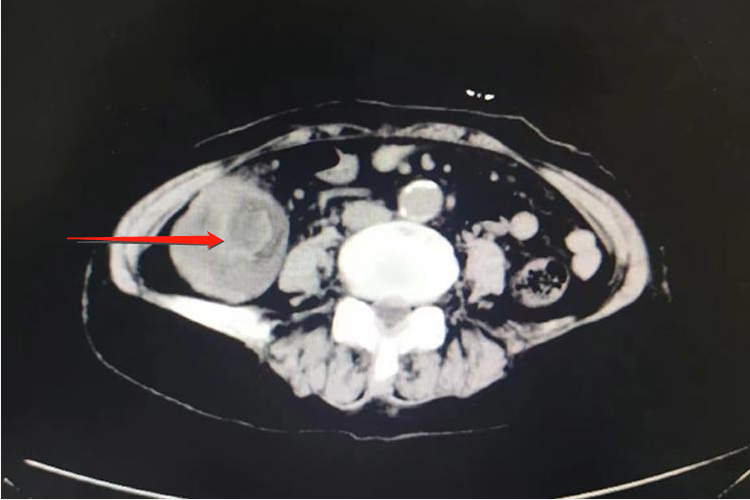

对于出现肠套叠的患者,CT检查常表现为腹腔内软组织肿块影,肿块呈高低密度相间的分层状或环状,分别代表套入部肠腔、肠壁、肠系膜脂肪及鞘部肠腔和肠壁,靶心为套入部的肠腔,其周高密度环为肠壁。增强扫描肠壁有明显强化。口服造影剂进入套入部,则靶心密度很高,CT表现以套入的肠系膜脂肪形成新月形或半环形的脂肪密度区最具有诊断特征。